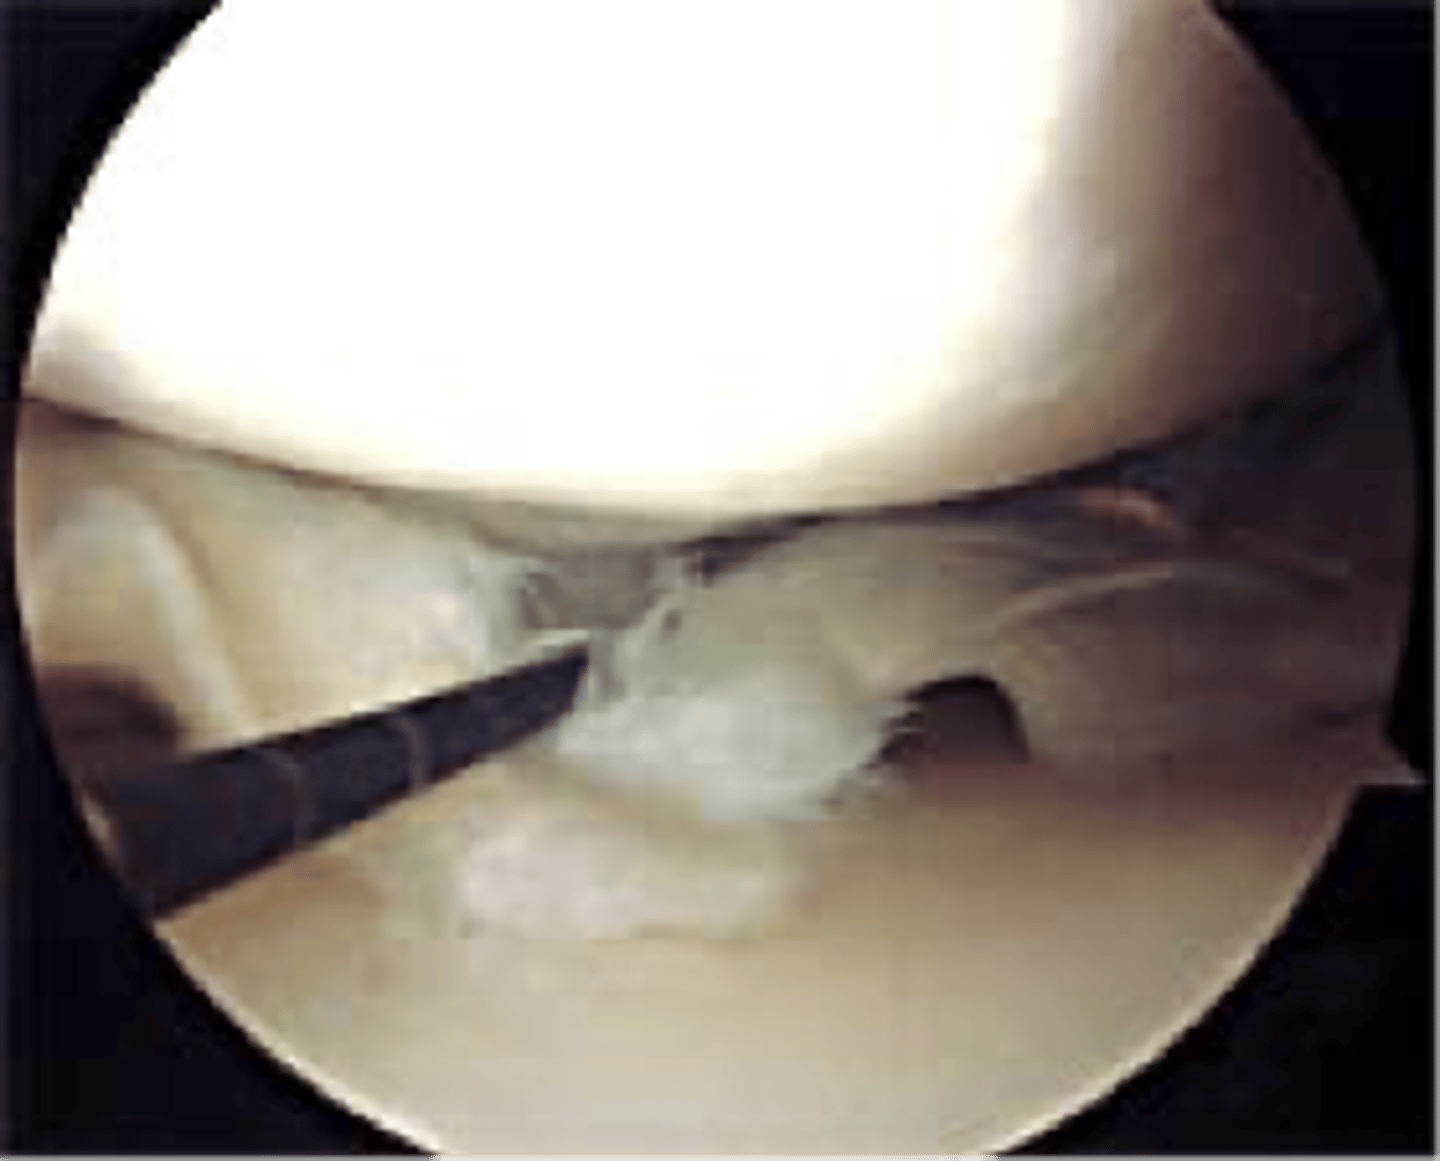

surgical treatment for meniscal tear

arthroscopic debridement or repair

How many ports enter the knee in arthroscopic surgery?

1. camera

2. irrigating instrument (lets in sterile saline)

3. trimming instrument